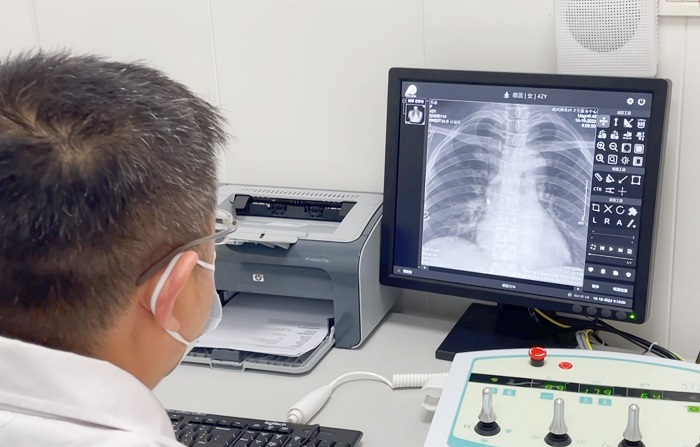

X射線機(jī)作為最基礎(chǔ)、最常用的影像檢查設(shè)備,也是體檢科必備的設(shè)備之一。體檢科人流量大,對于拍片設(shè)備的要求相對更加嚴(yán)格。普利德多功能動態(tài)平板DRF自進(jìn)入市場以來,以其性能穩(wěn)定、圖像清晰、快速成像等多種優(yōu)勢受到各級醫(yī)療機(jī)構(gòu)體檢科的青睞,尤其在應(yīng)對大規(guī)模、高流通量檢查中表現(xiàn)優(yōu)異!

不同于常規(guī)DR只能進(jìn)行平片攝影檢查,普利德多功能動態(tài)平板DRF動靜兼?zhèn)?,可?shí)現(xiàn)大幅面低劑量透視檢查,在日常的體檢工作中,比如胸部及肺部檢查,可對重疊部位病變進(jìn)行可視化觀察及多角度旋轉(zhuǎn)體位,發(fā)現(xiàn)疑似病灶可瞬時完成高清點(diǎn)片,顯著提高診斷的準(zhǔn)確性。

動態(tài)采集幀率最高可達(dá)30幀/s,影像細(xì)膩流暢,便于醫(yī)生對細(xì)微病變的觀察。17×17英寸大幅面成像,在透視過程中能對患者的胸部腹部等部位實(shí)現(xiàn)大范圍覆蓋,便于從整體上觀察組織信息,更加全面且精準(zhǔn)的捕捉病灶。